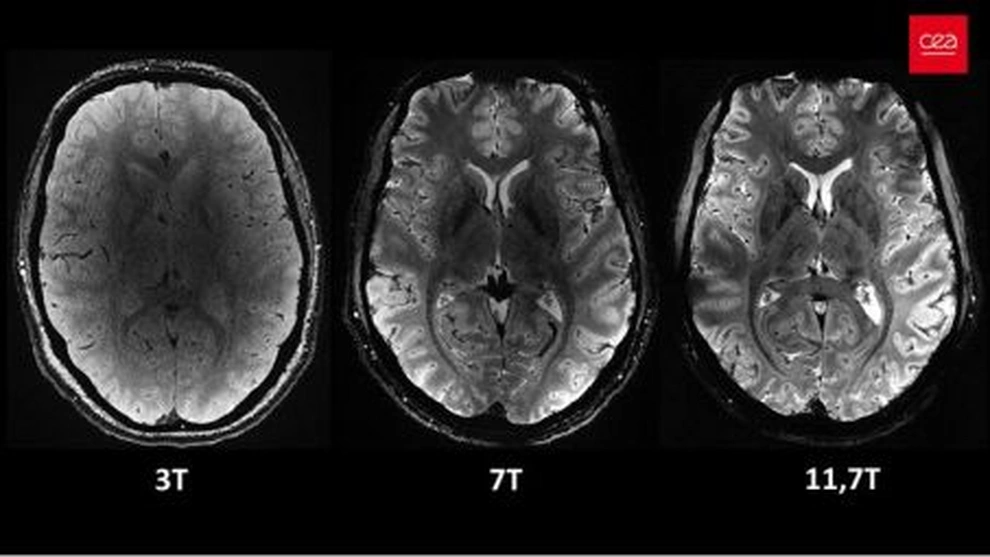

| Phần trục của não người (Ảnh: CES). |

Nhà nghiên cứu Anne Isabelle Etienvre (CEA), cho biết, cỗ máy này tạo ra từ trường kỷ lục (11,7 đơn vị Tesla), gấp 230.000 lần từ trường Trái Đất. Lưu ý rằng, từ trường càng cao thì độ phân giải của hình ảnh càng lớn.